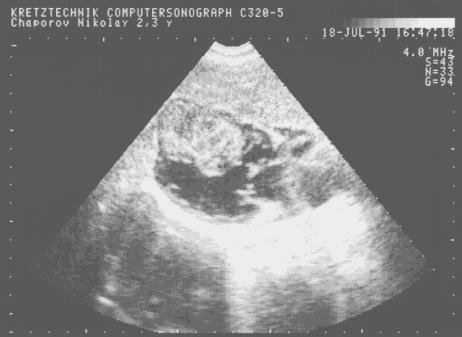

Миксома левого предсердия.

Рис.155

Миксома левого

предсердия: плотный

эхосигнал между

створками

митрального клапана

в диастолу.